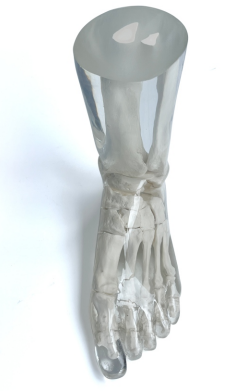

成人腿部模體,用于 X 射線 CT 和超聲波的成人腿部(肌肉)模型是一種基于人類男性腿部平均解剖結構設計的逼真模型。它具有所有基本的骨骼和

軟組織特征,使其成為學習、研究和測試醫學成像設備的理想工具。 模體可用于研究不同方向和定位技術的多種診斷性 X 射線 CT 和超聲程序。根據

要求,該產品可以根據不同的病理進行定制,也可以用于特定的培訓應用。 模體尺寸:965.2 x 254 x 177.8 毫米,重量:12kg(約)